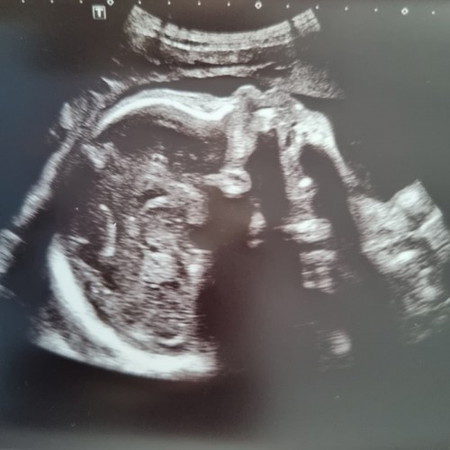

Growing well, week 29+4 He's so huge now, weighing at 1.4kg. Awaiting for your arrival babyS 👶 ♥️

Am glad that my baby is growing well, and head down position, despite my GD.